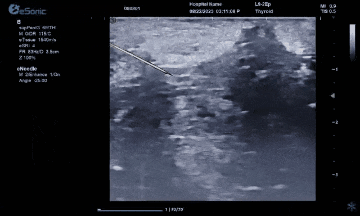

而准台式RTE弹性成像在超声介入应用中又是一大助力。操作简单、高实时性高重复性、通过颜色可直观评评估组织软硬程度。也有助于非肿块区域硬度异常的发现和评估。在穿刺中可引导穿刺到硬度较大的区域,提高穿刺阳性的成功率。

智能介入解决方案、无磁导航,可以在比较复杂的环境中,如ICU、其它床旁等场景下应用时,不会受周围机器的影响。另外,除了常规的穿刺针智能增强,支持针体增强程度调节外,智能穿刺针彩色Map技术又是银河官网医疗(ESI)准台式超声的首创技术。在超声引导穿刺消融的过程中,能够增强穿刺针与组织的对比度,清晰显示针尖与针体。